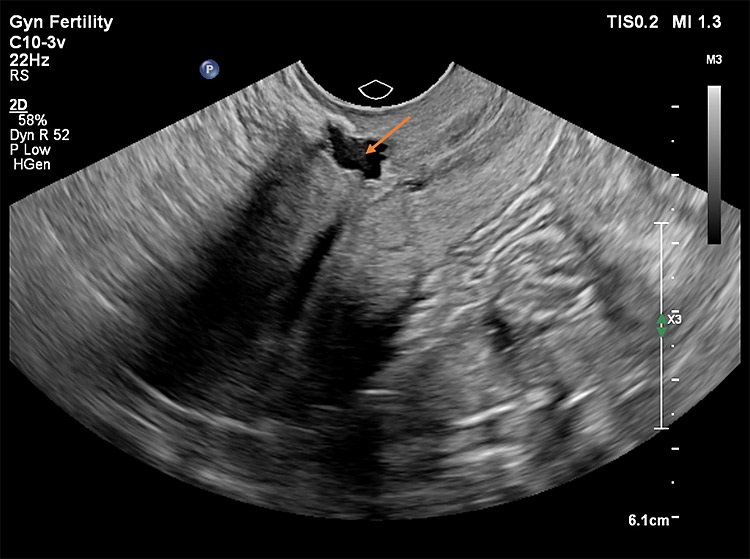

Στις παρακάτω εικόνες από ενδοκολπικό υπέρηχο φαίνονται παραδείγματα επιπέδου τρία προηγμένης τεχνολογίας υπερηχογραφικής μελέτης όπου σημαντικές λεπτομέρειες σε ό,τι αφορά τη θέση, το μέγεθος και την ανατομική συσχέτιση της Ισθμοκήλης, είναι εμφανή με καθαρό τρόπο, επιτρέποντας την εκτίμηση κατά πόσο μπορεί να γίνει χειρουργική επέμβαση ή όχι, και αν ναι με ποια τεχνική. Όλες οι εικόνες έχουν παραχθεί με υπερηχογραφική μηχανή Philips Elite, Costas Panayotidis operator.

Εικόνα 1 : Η ισθμοκήλη φαίνεται στο πάνω τμήμα της εικόνας που είναι μία κυστική μορφή όπου δείχνει το βέλος, γεμάτη με υγρό και φαίνεται ξεκάθαρα η ελαττωματική επούλωση.